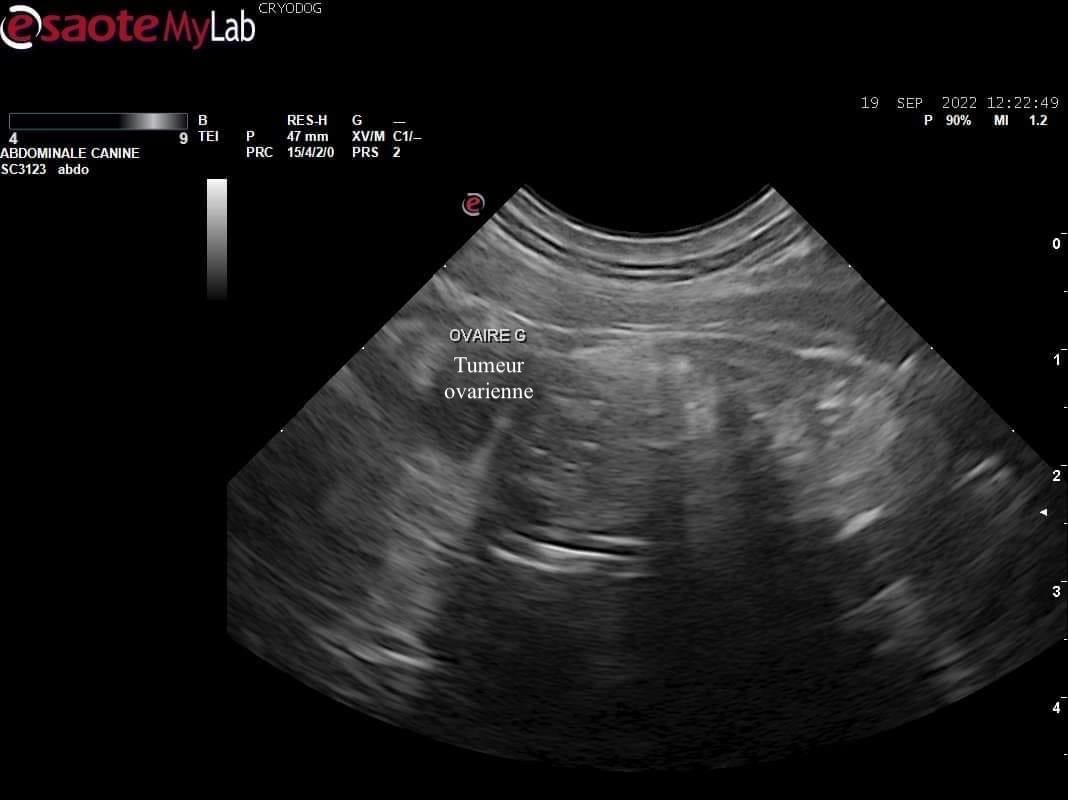

Lors d'avortements répétés ou d'infertilité chez la femelle, des prélèvements vaginaux (bactériologie et recherche quantitative de mycoplasmes), une échographie de l'appareil génital, un bilan hormonal ou un suivi rapproché de la gestation peuvent être indiqués pour établir un diagnostic et vous proposer une prise en charge de votre lice.